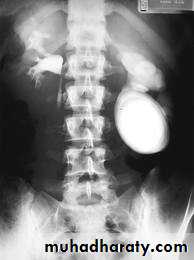

-Over 90% of calculi are radiopaque on plain films and virtually all on CT as very sensitive for detection of calculi, even those that appear radiolucent on plain film.-Most of these stones are a mixture of calcium oxalate and phosphate.

-Only pure uric acid and xanthine stones are radiolucent on plain x-ray but CAN be identified by CT or US, uric acid stones are associated with increased uric acid excretion in urine as in gout.

• Ddgx of stone on KUB :

• 1. Gall stone• 2. calfied LN , cartilage ,fibroid,

• 3. Phlebolith: round, lucent centre.